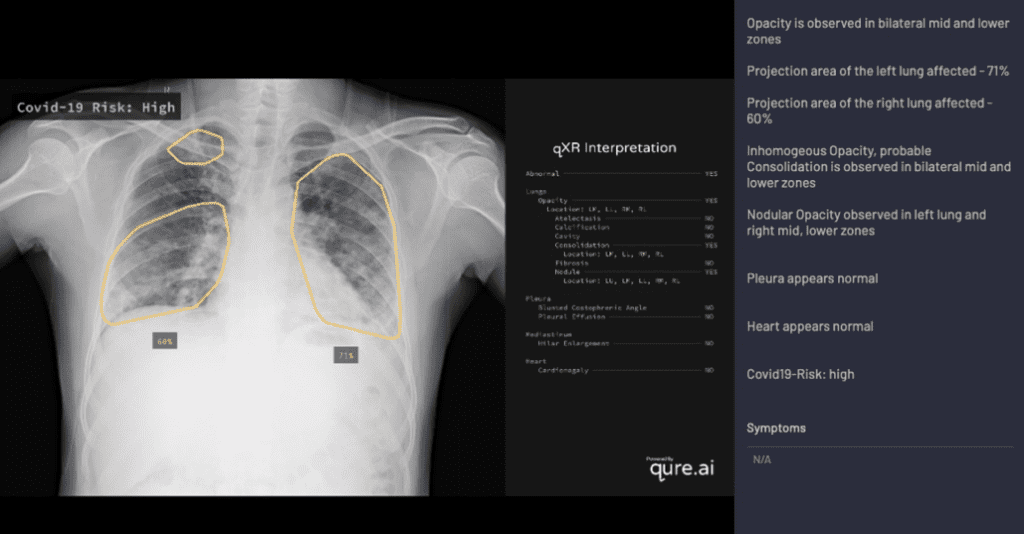

مصدر الصورة: كيور إيه آي

وعلى سبيل المثال، يستخدم نظام qXR من كيور إيه آي تركيبة من نماذج التعلم العميق لكشف الأنواع الشائعة من شذوذات الرئة. ولتعديله، عملت الشركة مع مجموعة من الخبراء لدراسة أحدث الأبحاث الطبية وتحديد الميزات النموذجية للالتهاب الرئوي الناتج عن كوفيد، مثل البقع البيضوية في الصورة، التي تتضمن نمطاً يشبه الزجاج المكسّر، إضافة إلى المناطق الكثيفة على جانبي الرئتين. قامت الشركة بعد ذلك بترميز هذه المعلومات ضمن qXR، وبهذا أصبحت الأداة قادرة على حساب احتمال الإصابة اعتماداً على عدد الصفات المميزة الموجودة في الصورة. وقد أجرت الشركة دراسة أولية للتحقق من صحة عمل النظام باستخدام 11,000 صورة للمرضى، ووجدت أن الأداة تمكنت من التمييز بين المرضى المصابين بكوفيد-19 وغير المصابين به بدقة 95%.